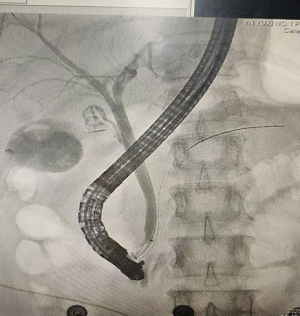

图片16

术中影像

9月19日,肝胆胰-甲状腺-血管外科医生为患者行“ERCP(经内镜逆行胰胆管造影)+EST(内镜下乳头括约肌切开术)+EPBD(内镜下乳头球囊扩张术)+胆管取石术+ENBD(内镜下鼻胆管引流术)+ERPD(内镜下胰管引流术)”手术。在内镜治疗下为患者取出胆总管结石,术后留置鼻胆管引流,两天后,患者拔除鼻胆管,一周后患者康复出院。